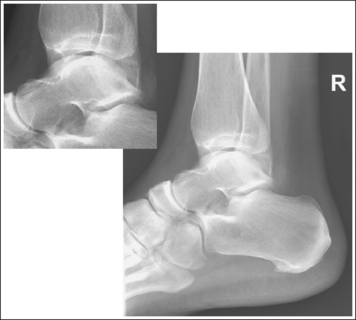

The calcaneus and distal tibia and fibula are in a lateral projection. The domes of the talus are superimposed, the tibiotalar joint space is open, and the distal fibula is superimposed by the posterior half of the distal tibia.

• Talar domes: The domes of the talus are formed by the most medial and lateral aspects of the talar's trochlear surface. They are visible on a lateral calcaneal projection as domed structures that articulate with the tibia. When a lateral calcaneus projection has been obtained, the talar domes should be superimposed and appear as one, and the tibiotalar joint should be open. If the lateral calcaneus is mispositioned, the domes are individually demonstrated and obscure the tibiotalar joint. Misalignment of the domes will result from poor knee and foot positioning.

• Effect of lower leg positioning on talar dome superimposition. Often, if the knee is not fully extended (Figure 6-42) or if the distal tibia is not elevated to place the lower leg parallel with the IR (in a patient with a large upper thigh), the proximal tibia is positioned farther from the imaging table than the distal tibia. The resulting image demonstrates the lateral talar dome proximal to the medial talar dome, and the height of the longitudinal arch appears less than it actually is because the cuboid shifts anteriorly and the navicular bone moves posteriorly in this position; the talocalcaneal joint will be narrowed (see Image 27). If the distal tibia is positioned farther from the imaging table than the proximal tibia, the medial talar dome is demonstrated proximal to the lateral dome, and the height of the longitudinal arch appears higher than it actually is because the cuboid shifts posteriorly, the navicular bone moves anteriorly, and the talocalcaneal joint will be wider (see Image 28).

When viewing a lateral calcaneal projection that demonstrates one of the talar domes proximal to the other, evaluate the height of the longitudinal arch and the degree of narrowing or widening of the talocalcaneal joint to determine which dome is the proximal dome. If the navicular bone is superimposed over more of the cuboid than expected and the talocalcaneal joint is narrowed, the lateral dome is the proximal dome; if the navicular bone is superimposed over less of the cuboid than expected and the talocalcaneal joint is wider, the medial dome is the proximal dome.

• Effect of foot positioning on talar dome superimposition. To demonstrate accurate AP alignment of the talar domes, the lateral surface of the foot should be positioned parallel with the IR. If this surface is not parallel with the IR, the talar domes are demonstrated with one anterior to the other. When the leg is rotated more than needed to place the lateral foot surface parallel with the IR, as shown in Figure 6-43, the medial talar dome is demonstrated anterior to the lateral talar dome (see Image 29). If the leg is not rotated enough to place the lateral foot surface parallel with the IR, as shown in Figure 6-44, the medial talar dome is demonstrated posterior to the lateral talar dome (see Image 30). When imaging a lateral calcaneus projection that demonstrates one of the talar domes anterior to the other, image the position of the fibula in relation to the tibia to determine how the patient should be repositioned. On most lateral calcaneus projections with accurate positioning, the fibula is positioned in the posterior half of the tibia. On a lateral calcaneus projection with poor positioning, if the fibula is demonstrated more posteriorly, the medial talar dome is anterior and the patient was positioned with the forefoot depressed and the heel elevated (leg externally rotated), as shown in Figure 6-43. If the fibula is demonstrated more anteriorly (leg internally rotated), the medial domes are posterior and the patient was positioned with the forefoot elevated and the heel depressed, as shown in Figure 6-44.